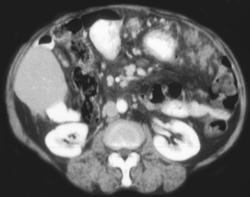

Serous Cystadenoma